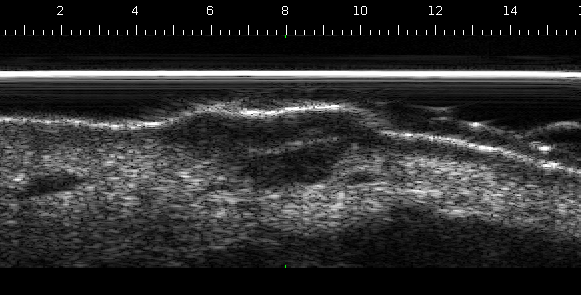

| Naevus in epidermis, 50MHz | Skin tumor, 50Mhz |

| Skin layers: epidermis, dermis, subcutaneous tissues, 25MHz | Kidney of a mouse, 25MHz |